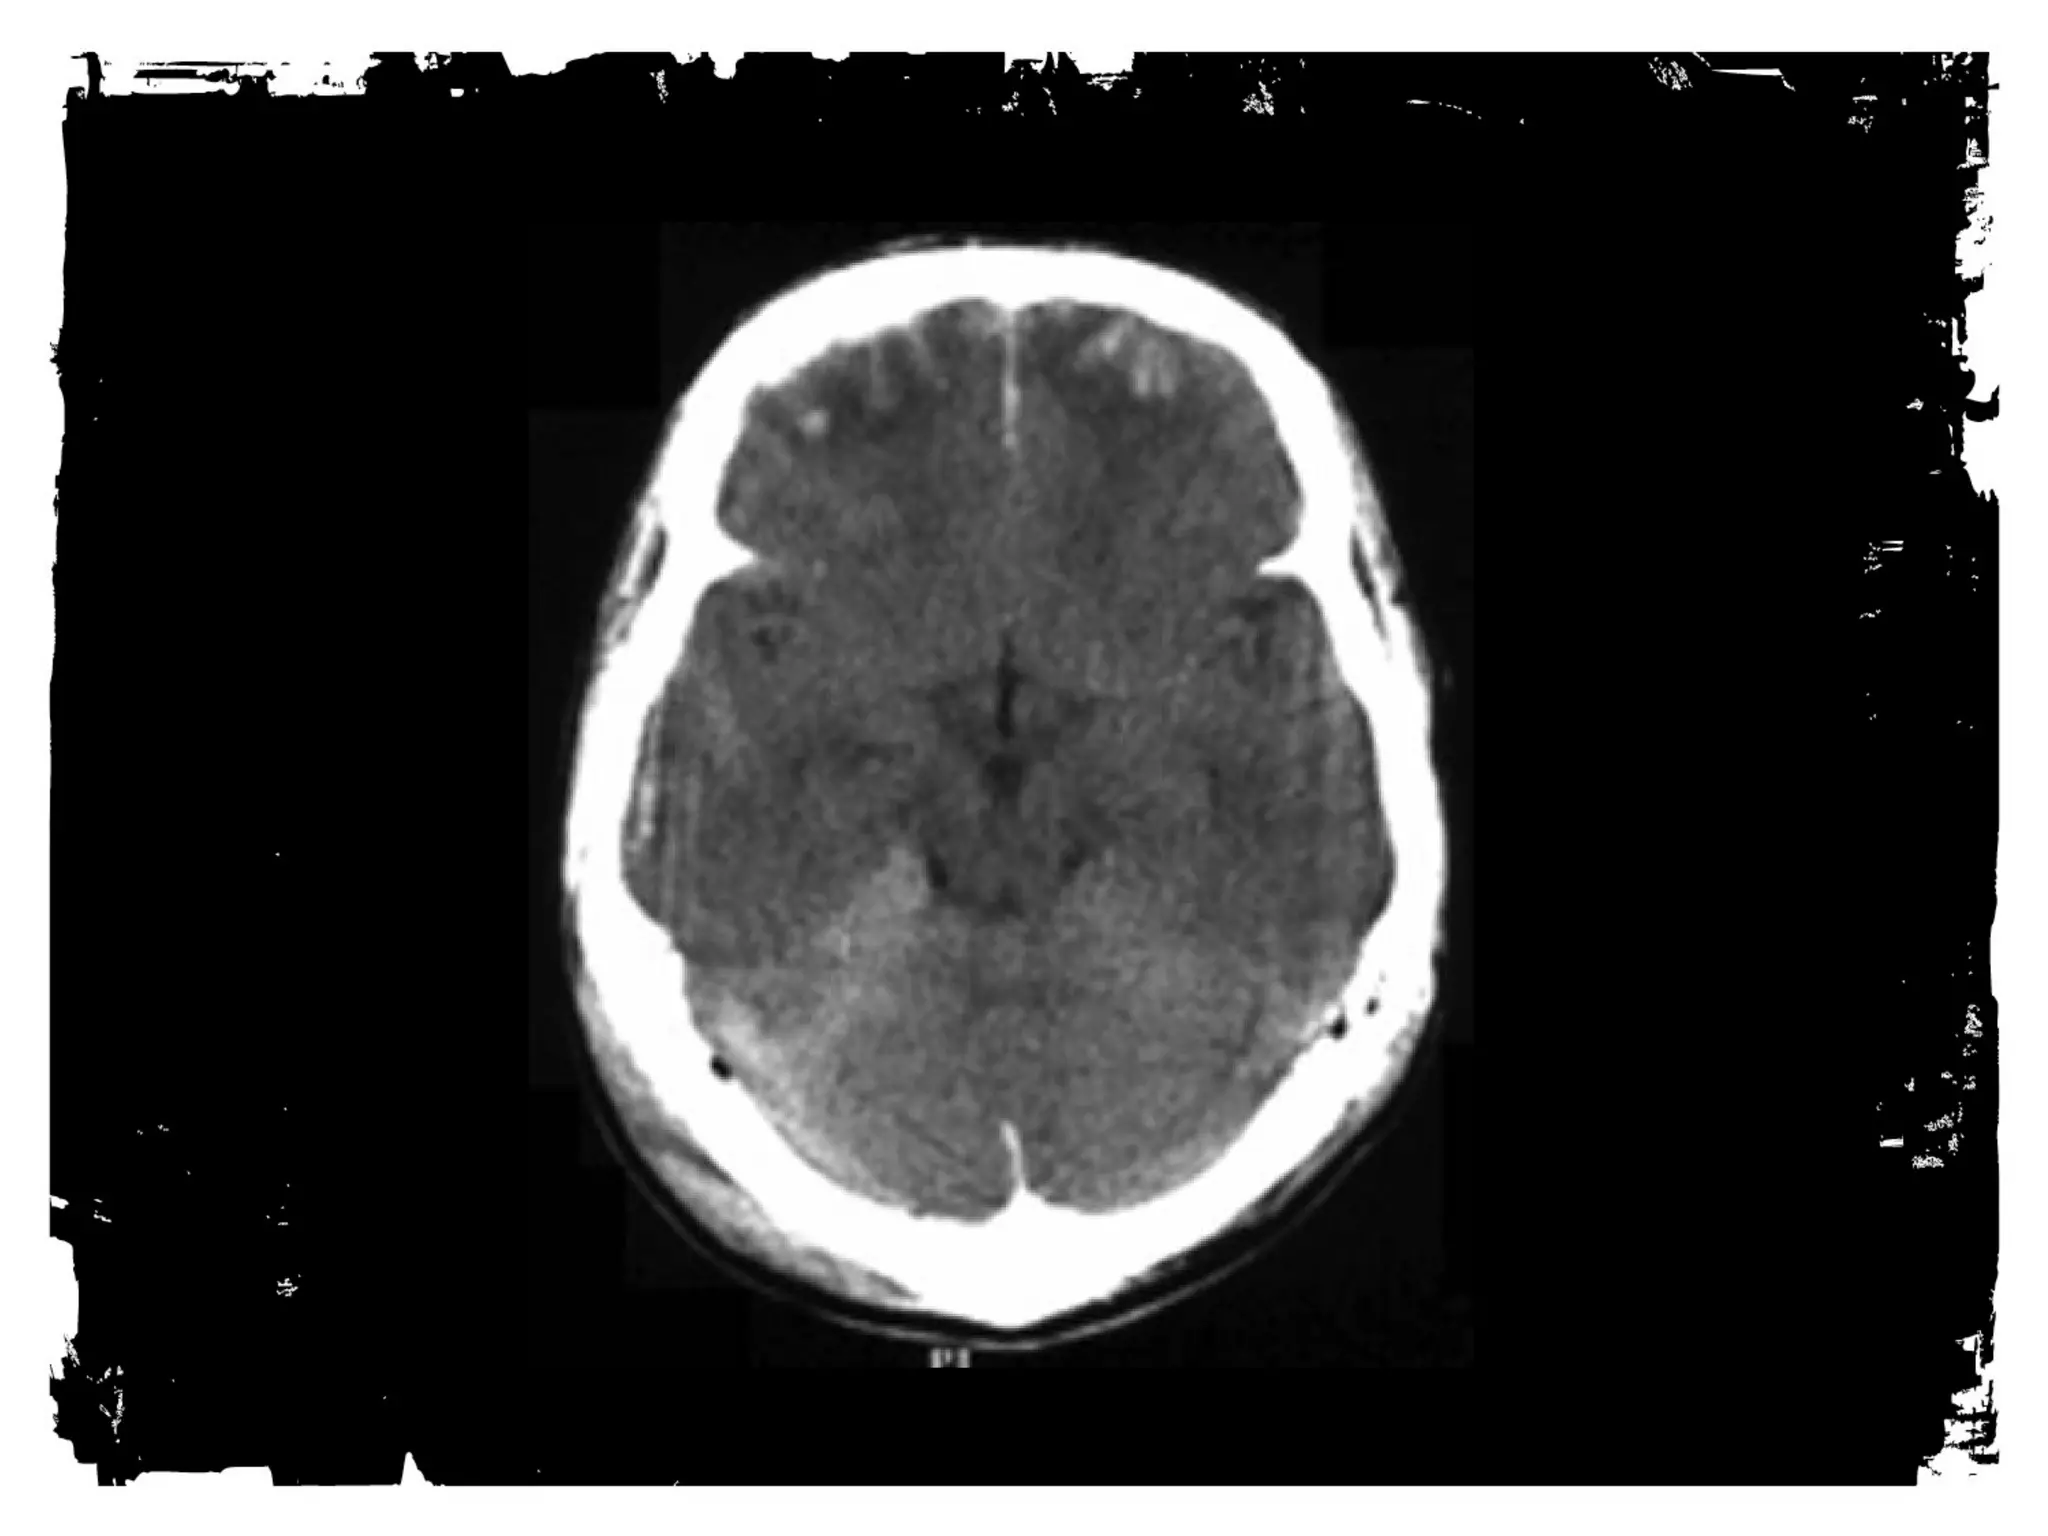

Head CT

Advantages for TBI include: availability, short scan times,

detailed anatomic information - including evaluation of facial

and temporal bone fractures.

Less sensitive for small parenchyma bleeds such as those seen

with DAI.

Diffuse axonal injury

Diffuse axonal injury (DAI) is a major form of traumatic

brain injury and is caused by shearing stress primarily in

white matter). Various outcomes are reported (ie, learning

disorders, moderate to severe disability, and vegetative

state) but were unable to correlate the extents of early

injury with the prognoses.

Among patients eventually

proven to have DAI, 50-80%

demonstrate a normal CT scan

upon presentation. Delayed CT

scanning may be helpful in

demonstrating edema or

atrophy, which are later

findings. Small petechial

hemorrhages located at the

gray-white matter junction, as

well as in the corpus callosum

and brainstem, are

characteristic of CT-scan

findings in the acute setting.